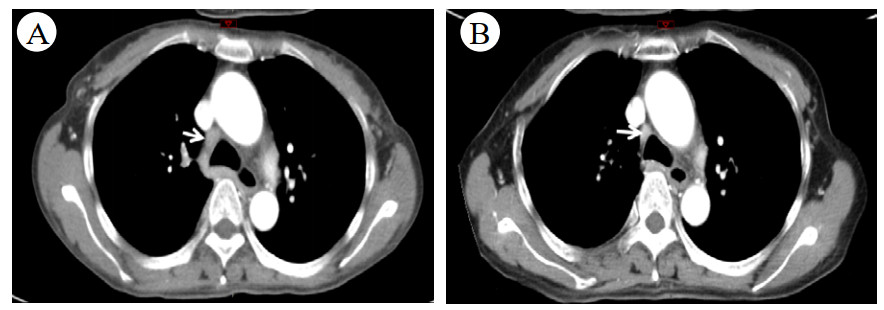

经过上述激素联合免疫抑制剂方案治疗,患者病情无改善,再次出现“发热、咳嗽”加重而就诊于当地医院,考虑肺部感染予泰能及莫西沙星静滴治疗11 d,效果欠佳并加重,鼻导管吸氧下动脉血氧饱和度仅及92%左右,故于2020-01-17转入本院ICU二科进一步诊治。入室时神志清晰,检查合作,浅表淋巴结未触及,腹软,上腹压痛。入室检查:血常规WBC 6.09×109,RBC 3.94×1012,Hb 107 g/L, PLT 33×109。总蛋白51.4 g/L,白蛋白24.16 g/L,总胆红素43 g/L,丙氨酸氨基转移酶339 U/L,门冬氨酸氨基转移酶191 U/L,肌酐34.87 umol/L,胆碱酯酶1346 U/L,降钙素原3.28 ng/mL,C反应蛋白193.5 mg/L,免疫指标阴性。D-DII 18 240 ng/mL,PT 17.1 s,APTT 42.8 s,FIB 5.08 g/L。CD4/CD8 > 1.25∶1。胸部CT示双肺间质广泛增厚并见多发斑片影,双肺肺门及纵隔见增大淋巴结,较图 2中影像增大、部分融合,见图 3。

| 图 3 2020-01-18 CT检查影像示纵膈的改变 |